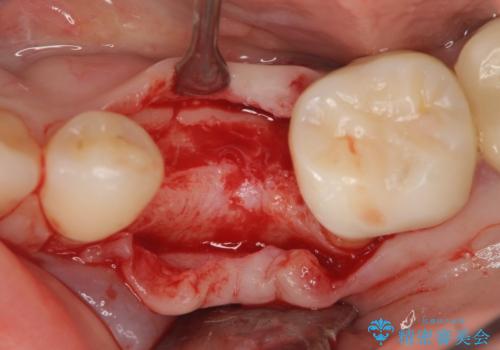

- 残していた乳歯がぐらつき始め、抜去ののちのインプラント治療を希望され来院されました。

乳歯を抜去して歯ぐきの状態が落ち着いたのち、骨の増成を伴うインプラント治療を行い機能の回復を図ります。